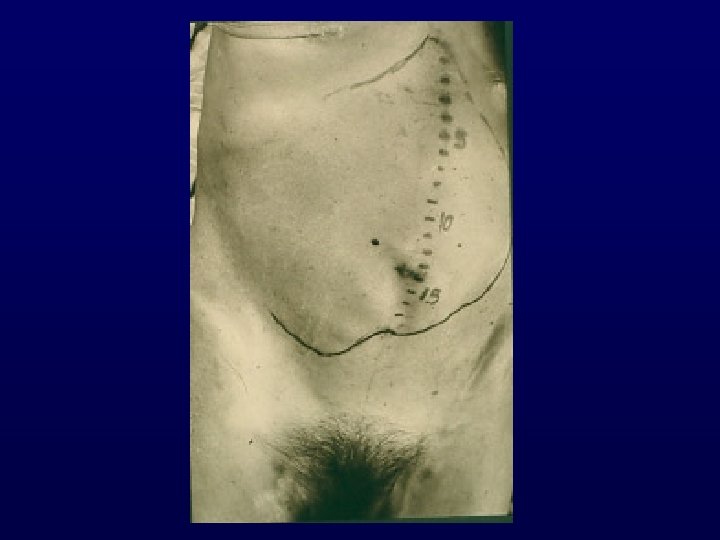

ISOLATED AXILLARY NODAL METASTASES FROM AN OCCULT PRIMARY BREAST CANCER

Years : 1975 – 2006 (24 studies) N : 689 patients Mean Age : 52 yr Menopause status : Postmenopausal 66% Premenopausal 34% Histology : Ductal adenocarcinoma 83%, ER/PR 40 - 50/%, HER 2 31% Nodal status : N 1 : 48% > N 1 : 52% Simultaneous distant mets : 2%

Treatment and Outcome ü Mastectomy / axillary dissection : 59 % ü Primary breast irradiation : 26 % ü Observation : 15 % ü Logoregional recurrence rate : 25 % (mostly in observation cases) ü 5 -yr Survival : 72 % (similar to stage II-III breast cancer) ü No survival difference between conservative management (breast preservation + RT) and mastectomy

TREATMENT RECOMMENDATIONS AXILLARY LYMPH NODE S u r g i c a l B i o p s y Compatible with Breast Cancer Mammogram U/S MRI +ve for Breast Cancer Standard treatment Type III level of evidence Other Neoplasm -ve for Breast Cancer Complete Axillary Dissection ± BC Surgery + Radiotherapy Chemotherapy or hormonotherapy depending on age and menopausal status